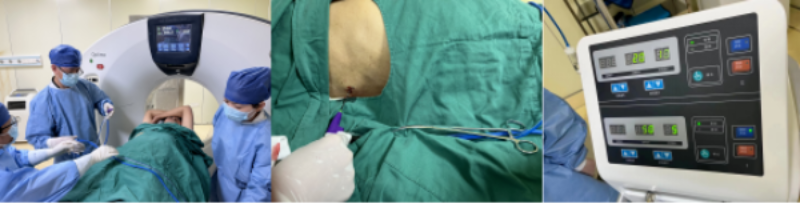

肝腫瘤鄰近橫膈,穿刺難度大,術(shù)前徐穩(wěn)深主任帶領(lǐng)腫瘤科專業(yè)團隊及放射科房志杰醫(yī)生為患者進行精準定位,設定穿刺路線

CT引導下微波消融治療過程